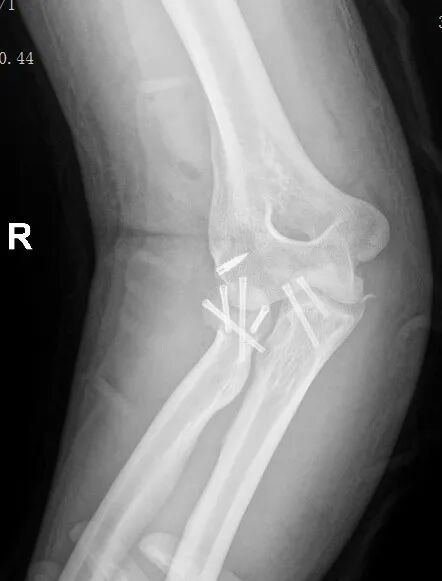

黄益平主任随即带领骨科团队进行了全面的评估和讨论,结合患者伤情及影像学检查结果,制定了精准的治疗方案: 右肘关节恐怖三联征骨折切开复位内固定+韧带重建修复肘关节稳定术。

手术过程中,黄益平主任凭借精湛的操作技巧和丰富的临床经验,带领团队顺利完成骨折复位、内固定植入及韧带修复等核心操作,每一步都精准到位,环环相扣。

术后复查提示:骨折对位对线良好,内固定位置理想。目前,郑先生正在医护团队的专业指导下开展循序渐进的康复训练,肘部功能逐步恢复,预后良好。

患者术后复查影像